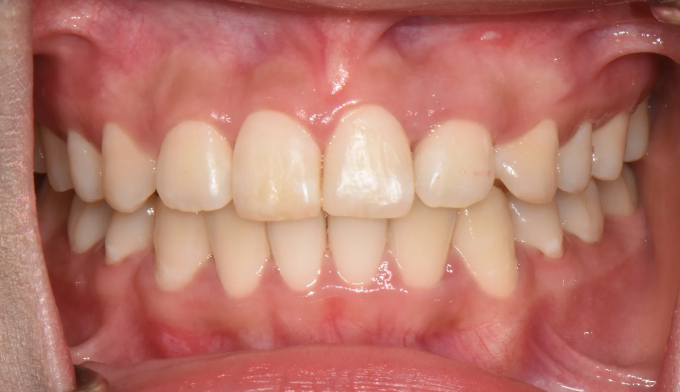

After

매복치의 경우 무조건 교정을 통해 구강내로 견인해야 하는건 아닙니다.

교정을 했을때의 득과 실을 살펴보는것이 중요합니다. 너무 깊숙히 묻혀있는 치아는 그냥 놔두는것이 나을때도 있습니다.

위쪽 송곳니가 엑스레이상에서도 거의 코 옆쪽으로 매복되어 있는 케이스입니다.

매복치에 접근하는것이 무리라고 판단되어 유치만 발치하고 진행하기로 하였습니다.

아래치아도 갯수를 맞춰주기위해 하나씩 발치하였습니다.